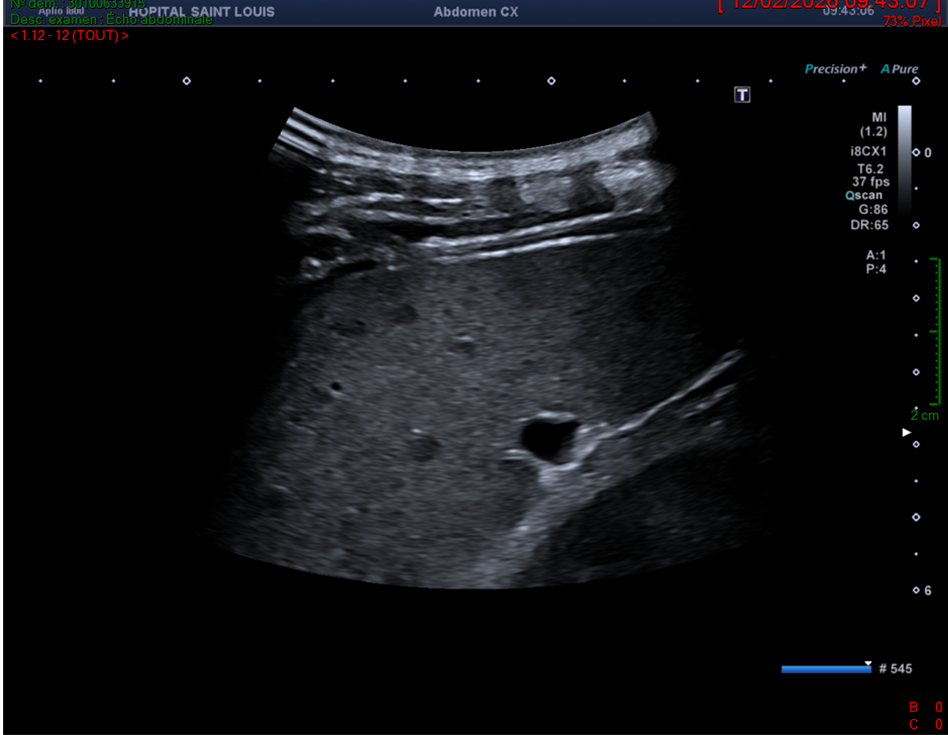

Rate avec utilisation d’une fréquence à 6.2MHz sur une sonde convexe.